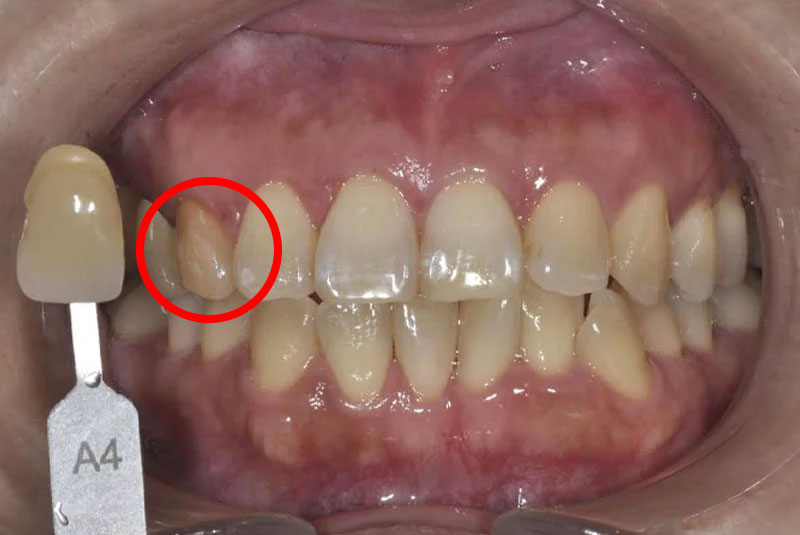

ウォーキングブリーチ後

Shade guideとの比較写真